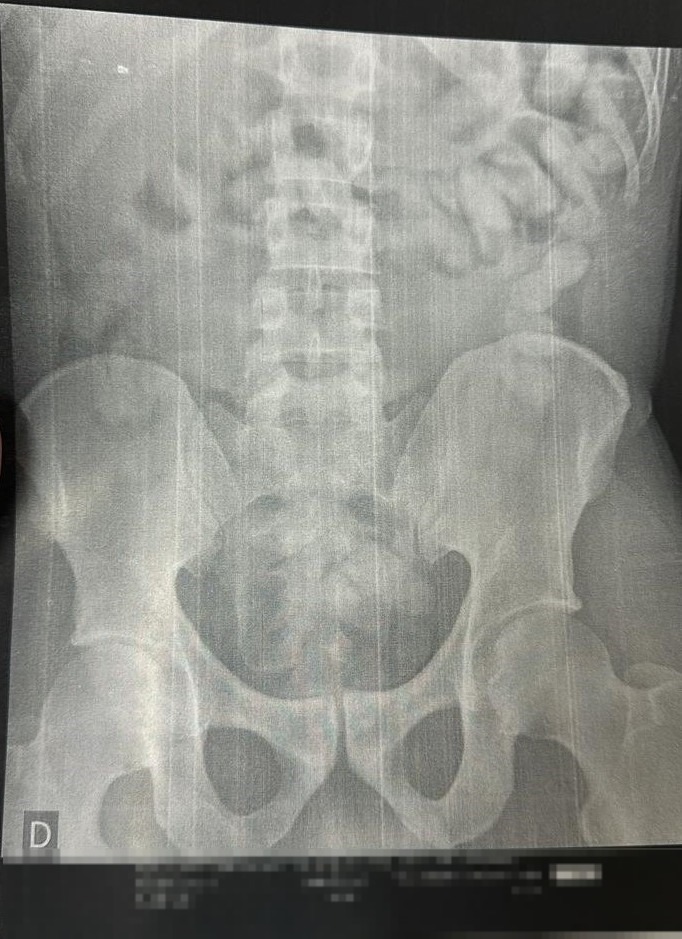

Durante a vistoria, o suspeito demonstrou nervosismo e confessou ter engolido mais de 100 cápsulas de cocaína. Ele foi encaminhado à delegacia para depoimento, quando passou mal e expeliu 21 porções. Em seguida, ele precisou ser levado ao Pronto Socorro.

No hospital, outras 106 foram retiradas durante uma cirurgia. A droga foi enviada ao Instituto de Criminalística (IC) para perícia.